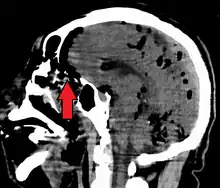

| Pneumocephalus and comminuted fracture of the frontal sinus |

Pneumocephalus is the presence of air or gas within the cranial cavity. It is usually associated with disruption of the skull: after head and facial trauma, tumors of the skull base, after neurosurgery or otorhinolaryngology, and rarely, spontaneously. Pneumocephalus can occur in scuba diving, but is very rare in this context.